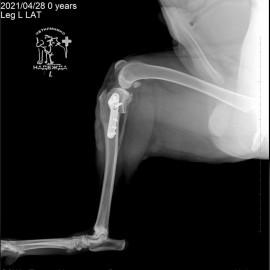

Собака породы хаски. Обратились с жалобами на хромоту на заднюю левую лапу. Были проведены исследования в ходе которых был поставлен диагноз: остеоартрит левого коленного сустава, разрыв передней крестообразной связки левого коленного сустава. Была проведена операция - TPLO.

Снимок 1 до операции